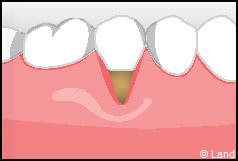

Les greffes de conjonctifs enfouis :

Destinées aux zones esthétiques, elles consistent à prélever la partie profonde du palais (site donneur).

Ce greffon est ensuite inséré sous la gencive au niveau de la récession (site receveur).